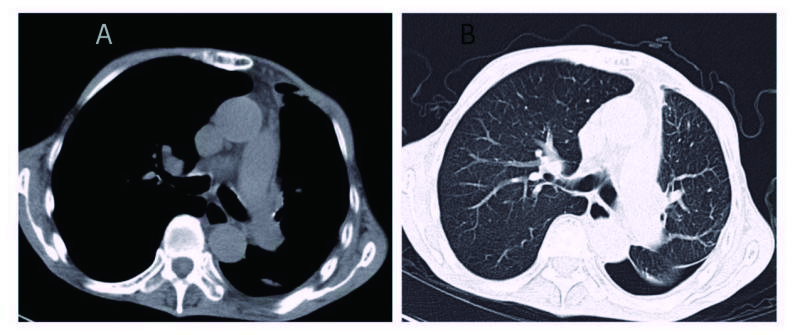

1 资料与方法患者男,70岁,农民,入院前3 d受凉后出现咳嗽,为阵发性干咳、无痰,伴胸闷、气喘,平卧及活动时加重,发热,体温最高37.7 ℃,热型未监测,无畏冷、寒战;当地医院胸部X线平片示左侧胸腔积液、左侧肺炎,予以“头孢噻肟”抗感染治疗无效,于2015年9月29日转来厦门大学附属第一医院。既往慢性支气管炎病史20余年,吸烟史50年×40支/d。入院时查体:T 37.6 ℃,P 106次/min,R 26次/min,BP 118/72 mmHg,SPO2 91%,神志清楚,反应迟钝,有时答非所问,呼吸较急促,气管轻度右偏;左侧胸部呼吸运动减弱,语颤消失,叩诊呈浊音,呼吸音减弱,右肺散在哮鸣音;心界不清,心率106次/min,节律规整,各瓣膜区未闻及杂音。入院后观察患者热型为不规则低热,查血尿粪常规、肝肾功能、肿瘤标志物等正常,降钙素原0.826 ng/mL,结核抗体及结核菌素实验阴性。血气分析:氧分压6.63 kPa,二氧化碳分压正常,无酸碱失衡表现。胸部CT示,双肺多发感染,左侧大量胸腔积液;右肺局限性肺大泡,肺气肿(图 1)。入院后给予莫西沙星抗感染,胸腔穿刺引流出大量淡红色稍混浊胸水,无臭味,每日引流量300~600 mL;胸水常规:李凡他试验阳性,蛋白48.6 g/L,有核细胞数1 520×106/L,比重1.021。患者仍有反复低热,热峰及持续时间稍改善。入院后10 d胸水培养结果回报为星型奴卡菌感染(图 3、4),抗生素更换为TMP-SMX 0.96 g/12 h联合红霉素0.25 g/8 h治疗,体温逐渐下降至正常,咳嗽、气喘症状缓解,胸水引流量逐渐减少至消失,PCT和血气分析结果恢复正常,胸部CT:左侧少量胸腔积液,伴积气(图 2)。于2015年10月25日出院,继续口服TMP-SMX片及红霉素片治疗,定期随诊。患者感觉恢复良好在出院后1个月左右自行停药,3个月后因右侧肢体无力再诊我院,颅脑MRI提示:大面积小脑梗死,脑疝并幕上脑积水(图 5),再诊时未再复查胸部CT,2 d后因呼吸循环衰竭死亡,家属未同意尸检。

| 图 1 左肺大量胸腔积液,左肺压缩近不显影(A:纵隔窗; B:肺窗) |

| 图 2 胸腔穿刺术后,可见左肺复张,双肺纹理清晰,伴少量积气(A:纵隔窗; B:肺窗) |